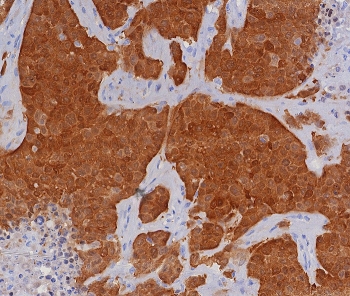

Immunohistochemistry of P16INK4a antibody in human cervical carcinoma tissue. The recombinant rabbit mAb clone CDKN2A/8196R shows strong, diffuse nuclear and cytoplasmic HRP-DAB brown staining in malignant epithelial cells, a pattern commonly associated with dysregulated RB pathway signaling in cervical neoplasia. Tumor cells display uniform positivity with sharp contrast against adjacent non-neoplastic stromal and inflammatory cells, which remain largely unstained. Heat-induced epitope retrieval was performed by boiling tissue sections in pH 9 10mM Tris with 1mM EDTA for 20 minutes followed by cooling prior to antibody incubation.